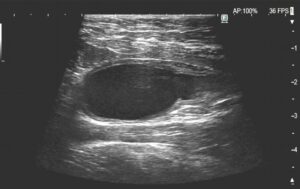

※術後点滴通院を行ってきれいになった膀胱(5/8)